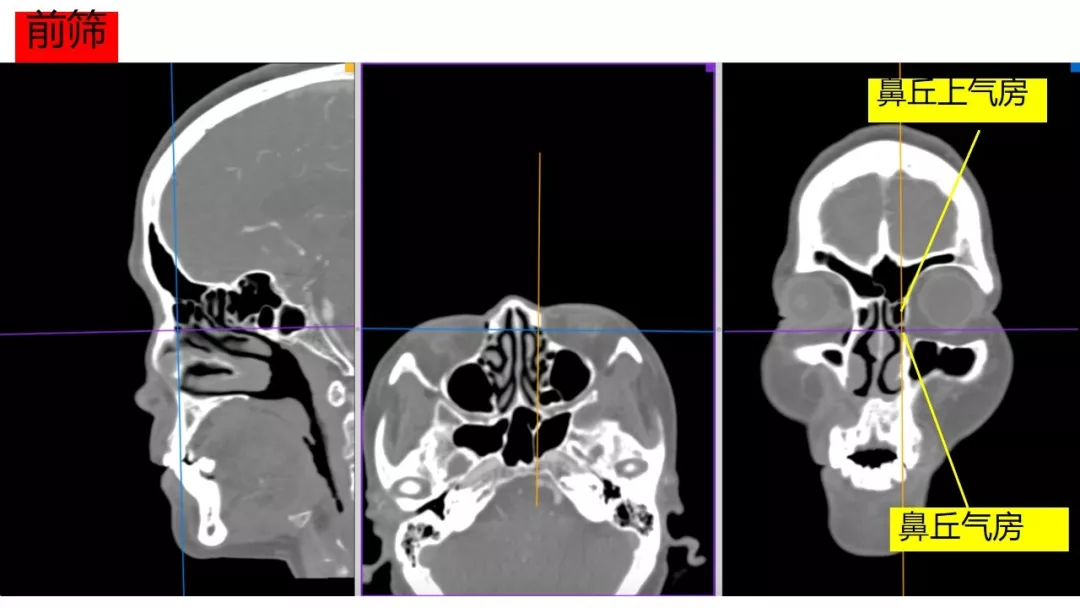

今日与大家分享的是《正海-妙术视界》第一百三十二期,由唐都医院神经外科赵天智、郭为、贺世明、屈延、高国栋带来的精彩手术:“前床突磨除与脑脊液漏处理---中鼻道经筛入路解剖、阅片与手术”,欢迎观看、分享。

内镜修补